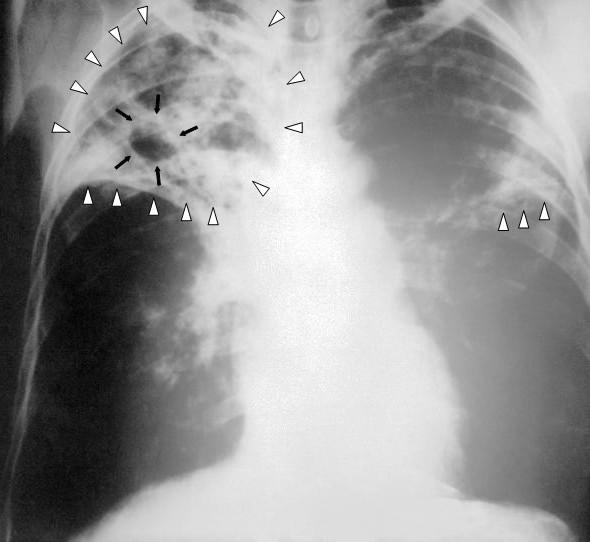

Tuberculoza, care afectează cel mai frecvent plămânii, este o boală infecțioasă cauzată de bacteria Mycobacterium tuberculosis, numită și bacilul lui Koch, după numele descoperitorului său.